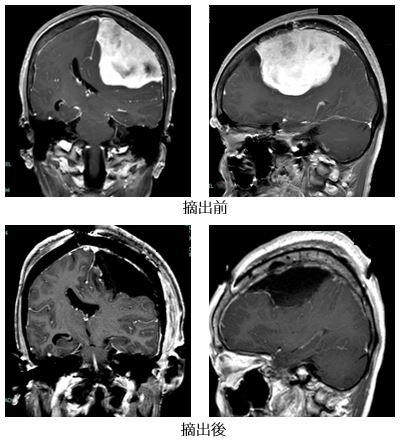

最も頻度が高い脳腫瘍で、脳を覆っている膜から発生します。多くは良性でゆっくり発育しますが、一部に成長が早い悪性のタイプが存在します。経過中に増大する場合や、圧迫による神経症状(てんかん、麻痺など)や脳浮腫が見られる場合は摘出手術を検討します。